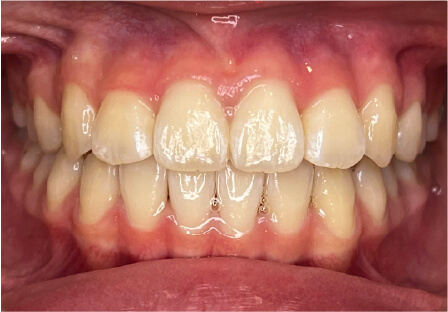

叢生の症例

41歳

女性

相談内容

横から見た時のガタガタが気になる

カウンセリング・診断結果

インビザライン、正中は上11に合わせていく、抜歯・拡大装置・IPR・アタッチメントOK

治療内容・方法

アライナー矯正

術後の経過・現在の様子

クリアライナー使用

治療のリスク

痛み・歯根吸収・歯肉退縮・虫歯・後戻り

費用・治療期間

880,000円、7ヶ月